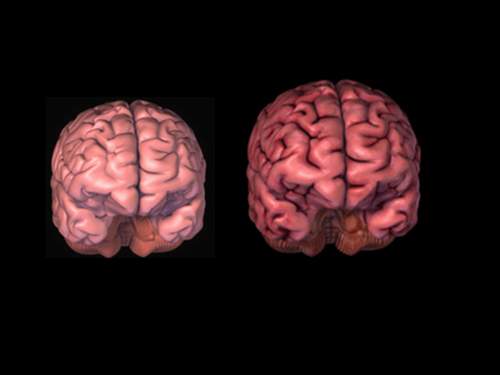

إذا قمنا بوزن دماغ رجل ودماغ امرأة سنجد أن دماغ الرجل أثقل بنسبة لا تقل عن 10 بالمئة وقد تصل إلى 20 بالمئة أحياناً، وهذا اختلاف يُضاف للاختلافات الكثيرة بين الرجل والمرأة. وحتى نسبة موت الخلايا في الدماغ تختلف من الرجل إلى المرأة، وطريقة عمل هذه الخلايا تختلف، فقد وجد الباحثون أن نسبة انكماش الدماغ (تنكس الخلايا) عند الرجل أكبر منه وأكثر وضوحاً من المرأة مع تقدم العمر. وهكذا اختلاف في كل شيء تقريباً..

يبين هذا المخطط تغير وزن الدماغ مع تقدم العمر، الشكل الأعلى يوضح تغير وزن الدماغ مع تقدم العمر منذ الولادة وحتى عمر 86 سنة، والشكل السفلي يبين النسبة المئوية لوزن الدماغ بالنسبة لوزن الجسم وكيف تتغير مع تقدم العمر. ويتبين لنا أن دماغ الرجل أكبر من دماغ المرأة. ويتبين كذلك أن نسبة وزن دماغ المرأة إلى وزن جسدها تكون هذه النسبة أكبر عند النساء بقليل من الرجال.

بينت الدراسات أن حجم دماغ الرجل أكبر من حجم دماغ المرأة عند نفس العمر، وذلك بعشرة إلى عشرين بالمئة، وهذه الزيادة عند الرجل في حجم دماغه تجعله مختلفاً عن المرأة في الكثير من العمليات الدماغية.